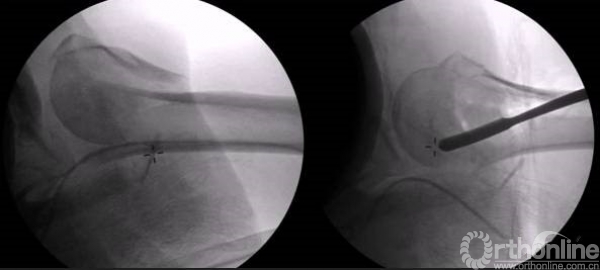

正位的翘拨复位

腋位的翘拨复位